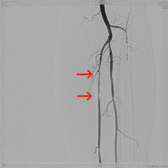

可怕的LEADDP 糖尿病下肢血管病变(LEADDP)可致患者肢体麻木、疼痛,间歇性跛行,乃至坏疽(糖尿病足),截肢率高达40 %以上。LEADDP是糖尿病致残、致死的主要原因,糖尿病患者因LEADDP造成的截肢,要比非糖尿病患者高5到10倍以上。先进的DSA + 微创介入 1、选择性血管造影(DSA)是LEADDP诊断的金标准。 2、微创介入治疗优点: 创伤小,仅有一2-3 mm的穿刺创口 成功率高:目前其成功率达85-90 % 保肢率高:术后病人截肢率可从40 %降为4 %左右 早发现早治疗:越早治疗效果越好.独创的微创介入 + HBO + bFGF综合治疗途径 1、DSA + 微创介入 2、高压氧(HBO)物理疗法:大型空气加压舱,治疗压力0.2 MPa,面罩吸纯氧30 min 3、基于重组成纤维细胞生长因子(bFGF)局部换药.